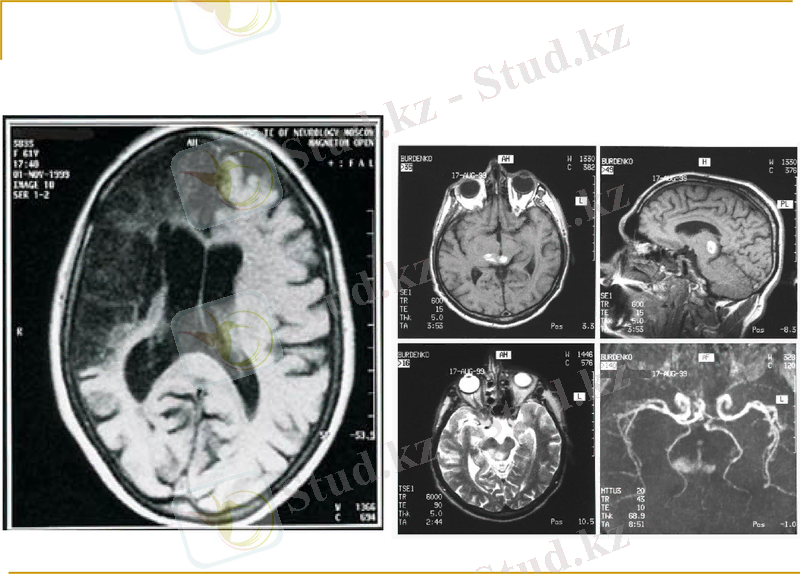

Инсульт кезіндегі магнитті резонансты томография:

МРТ инсультті анықтаудың негізгі әдістерінің бірі. МРТ-қатты, сұйық және газ тәріздес денелерде радиожиілік диапазонындағы электромагниттік энергияның резонанстық жұтылуы. Мұндай резонанстық жұтылу құбылысы сыртқы магнит өрісіне орналасқан зат ядроларының магнетизміне байланысты пайда болады. Резонанстық жиіліктегі радиожиіліктік өріс ядролардың айналуы бағытын өзгертеді, яғни ядролық магниттелушіліктің қозғалысын тудырады. Бұл қозғалыс зерттелінетін затты қоршаған индуктивтілік орамада пайда болатын индукциялық ЭҚК арқылы анықталады

Инсульт кезіндегі МРТнің артықшылығы :мидың сұр заты мен ақ затының контрастты көрінісі анық көрінісі, базальды, қыртысты, милы құрылымдарының анықтылығы, сонымен қатар компьютерлік томографиядан ерекшелігі гиппокамп пен мидың үлкен сыңарларының күштірек көрінісі мен ми инфарктысының ерте кезеңдерін анықтауда шешуші рөл атқарады.

МРТ ның Кт дан қарағанда майда лакунарлы инфаркттарды анықтауда әлдеқайда тиімдірек. Бірақ Мрт-ның жүргізілу уақыты кт-ға қарағанда ұзағырақ болғандықтан, жедел мидың қанайналым жетіспеушілігі кезінде кт-ны жүргізу бірінші орында тұрады.

Сонымен қатар МРТ мен қоса инсульт диагностикасы кезінде МРА (магнитті резонансты ангиография) да жүргізіледі. МРА кезінде мидың қан тамырларының жағдайын анық көруге болады. Бірақ МРА қалыпты ангиографиядан сезімталдығы тұрғысынан қалып қояды. Алайда бұл әдіс инвазивті емес болғандықтан жиі қолданылады.